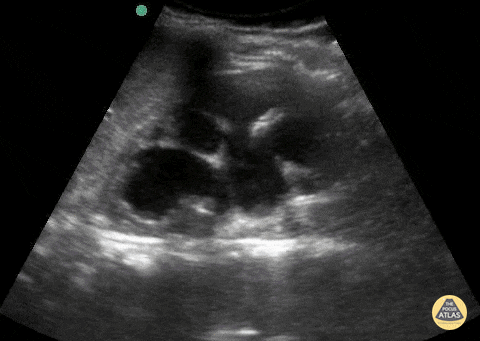

11 year old male presenting for left flank pain and headache. POCUS with severe left sided hydronephrosis without stone. Contributor: Matthew Moake, MD PhD